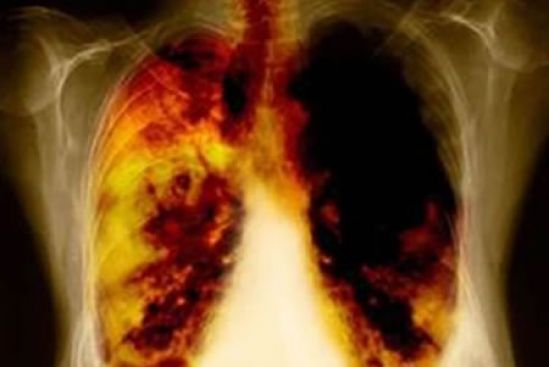

El especialista explicó que cuando el tumor crece e invade el bronquio, los síntomas son tos con sangre; al invadir la membrana que rodea al pulmón, conocida como pleura, puede ocasionar la generación de líquido pleural y, en consecuencia, falta de aire de la persona afectada.

Una vez diseminado el cáncer, el enfermo pierde peso y siente malestar general. Cuando dicha metástasis se registra en hueso -uno de los lugares más frecuente- puede ocasionar dolor, y es el momento en que la persona acude al servicio médico.